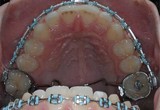

Klasické kovové zámky jsou stále nejpoužívanější zámky v České republice. Nejsou již ale nejmodernější. V nezměněné podobě jsou na trhu téměř 50 let. Za tuto dobu se změnily požadavky na estetiku úsměvu. Po vyrovnání zubů tímto typem rovnátek není úsměv tak krásný a moderní, jako při použití modernějších typů rovnátek (Foliová rovnátka, DAMON systém). Kovové zámky s barevnými gumičkami již používáme pouze u dětí do 10 let.

Mezi základní součásti fixních aparátů patří kroužky na zadních zubech (nemusí být vždy) a na předních zubech nalepené zámky. Do zámků je vložen drát, který vyrovnává zuby a je k zámkům upevněn ligaturami. Ty mohou být gumové (barevné i bezbarvé „gumičky“) nebo kovové. Ligatury svým velkým třením zpomalují pohyb zubů. Proto existují též tzv. samoligovací zámky, např. DAMON, které ligatury nepotřebují a tudíž je léčba s nimi rychlejší a mají i spoustu dalších výhod.